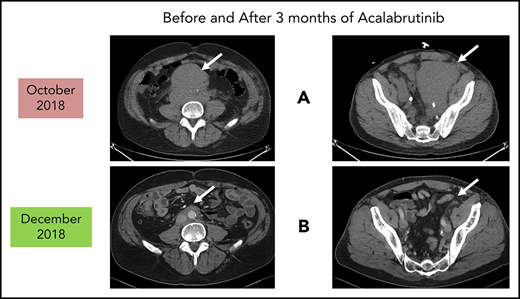

Before and after 3 months of acalabrutinib. A 54-year-old man was diagnosed with stage IVB MCL in 2014. He received chemoimmunotherapy including cytosine arabinoside and an adjuvant autologous SCT. (A) In 2018, he relapsed with left leg swelling due to bulky pelvic disease and a new deep vein thrombosis. (B) After biopsy proof of relapsed MCL, he received acalabrutinib 100 mg twice daily, rituximab, and apixaban; within 3 months, he achieved a marked response with no side effects of the combination. He has returned to full-time work and continues on therapy as of January 2019.

Patients who relapse are typically treated with salvage chemoimmunotherapy or other approved agents. These include the proteasome inhibitor bortezomib,13,14 the immunomodulatory agent lenalidomide,15-19 the mammalian target of rapamycin complex 1 inhibitor temsirolimus (Europe, not United States),20-24 and the Bruton tyrosine kinase (BTK) inhibitors discussed in the next section.25-29 The bcl-2 inhibitor venetoclax has orphan drug designation (but not approval) for MCL.30,31 Despite the plethora of agents for this disease, most patients will need all of them during their lifetime. Thus, there is always a need for additional agents as illustrated by the case described in Figure 1.

As reported in the clinical trial,43 acalabrutinib at the recommended dose of 100 mg twice daily is well-tolerated as demonstrated by only 1.6% of patients requiring dose reductions and only 6.5% of patients discontinuing acalabrutinib due to adverse events. Of note, atrial fibrillation was not observed in any patient. The most common side effects were headaches (36%) and diarrhea (38%), both of which were typically grades 1-2 and self-limited.43,44 If treatment of these is needed, then oral nonnarcotic agents that do not impair platelet function are recommended. These would include acetaminophen alone or with caffeine. Bleeding events were usually grade 1-2 and consisted of bruising and petechiae; there was 1 case of grade 3 gastrointestinal hemorrhage. Significant myelosuppression can occur and grade 4 neutropenia occurred in 6%. For these grade 3/4 toxicities, dose reductions to 100 mg daily may be required. It is not known what effect dose reduction has on tumor response. In patients such as the 1 described in Figure 1, acalabrutinib at full dose can be given with direct oral anticoagulants with appropriate instructions to watch for bleeding complications.